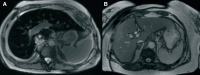

Case summary: We present the case of a 41-year-old female who was hospitalized for decompensated HF. Echocardiography revealed severe systolic dysfunction with a phenotype of dilated cardiomyopathy, accompanied by secondary moderate mitral regurgitation and severe tricuspid regurgitation (TR). To differentiate potential causes of HF, coronary angiography, cardiac magnetic resonance imaging (MRI), and endomyocardial biopsy were performed. Based on clinical findings, laboratory results, cardiac MRI, and endomyocardial biopsy data, a diagnosis of haemochromatosis was confirmed, and mutations in the TFR2 gene, responsible for haemochromatosis Type 3, were identified. The patient was treated in accordance with the latest European Society of Cardiology HF guidelines, and specific treatment for haemochromatosis, including therapeutic phlebotomy and iron chelation therapy, was initiated, resulting in a significant positive outcome.